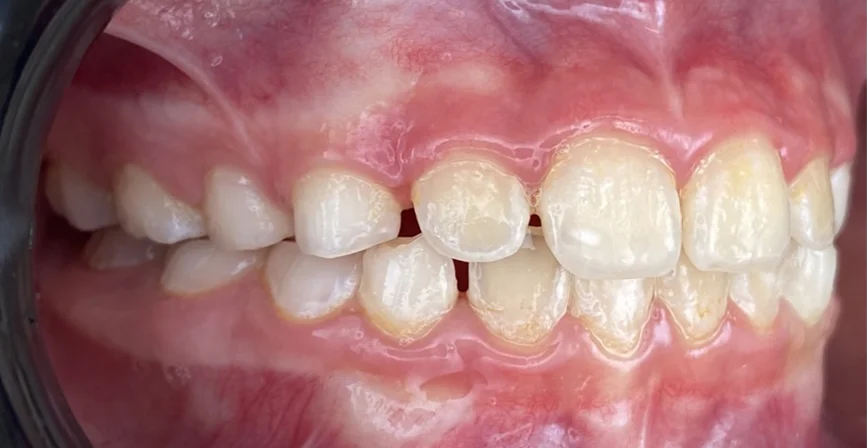

Търсейки детски ортодонт, пациентът дойде с основни оплаквания – “Долните зъби са пред горните” Кръстосаната захапка във фронта, затруднение при отхапване, нарушена естетика.

Кръстосана захапка във фронталния участък

Компресия на челюстите

Струпване и липса на място за пробива на постоянните зъби

- Интраорални и екстраорални снимки